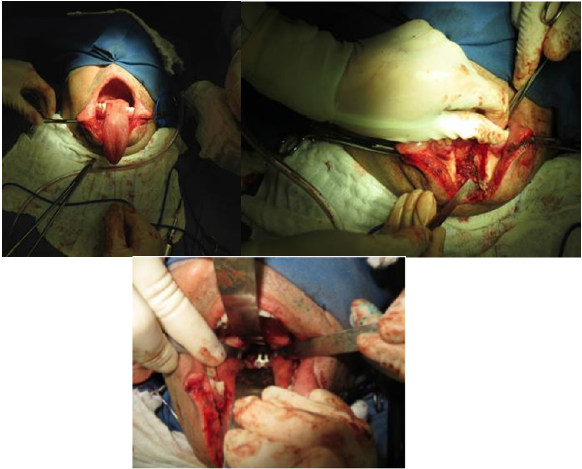

Five months after the second intervention, the patient presented global neurological deficit with signs of myelopathy (loss of balance and fine movements). A mandibular osteo to my by the transoral approach was performed, when the cervical vertebra lesion was resected, besides making an incision in the chin region, with para cervical extension for Odontoid body resection and of CII/ CIII vertebral discs. Still at this stage, there was the very patient’s fibula grafting, and cervical plate with screws in the CIII body, with posterior mandibular repositioning and rigid fixation of symphysis.

Figure 5: Intra operative pictures.